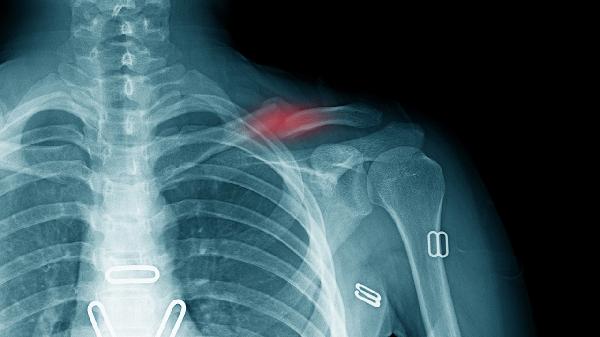

骨折后可在医生指导下使用接骨七厘片、伤科接骨片、仙灵骨葆胶囊、碳酸钙D3片、阿法骨化醇软胶囊等药物促进恢复。骨折通常由外伤、骨质疏松、骨肿瘤等因素引起,需结合影像学检查明确损伤程度,药物需严格遵医嘱使用,不可自行调整剂量或更换药物。

骨折恢复期需保证每日摄入牛奶、鱼类、深绿色蔬菜等富含钙和优质蛋白的食物,避免吸烟饮酒。根据康复阶段在医生指导下进行渐进式功能锻炼,如早期肌肉等长收缩、中期关节活动度训练等。定期复查X线观察骨痂生长情况,若出现患肢麻木、异常疼痛需及时复诊。卧床患者需预防压疮和深静脉血栓,保持适度阳光照射以促进维生素D合成。